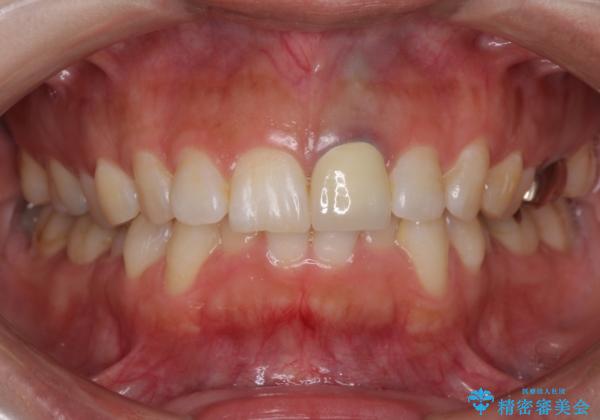

色は完全にとるのが不可能であることをご了承頂いた上で、土台と被せものの治療を行いました。

今回は歯自体が黒くなって歯茎から透けて見えている黒ずみのため、セラミック治療で改善させることは困難だというお話をしました。その上でできる範囲できれいに治療することになりました。

今回のように歯自体が金属イオンで黒く変色すると、被せものをメタルフリーにしても黒ずみをすべて隠すのは困難になります。一方、被せものの金属が見えていることが原因の黒ずみの場合は、セラミック治療できれいになりますので、気になる方は一度ご来院ください。